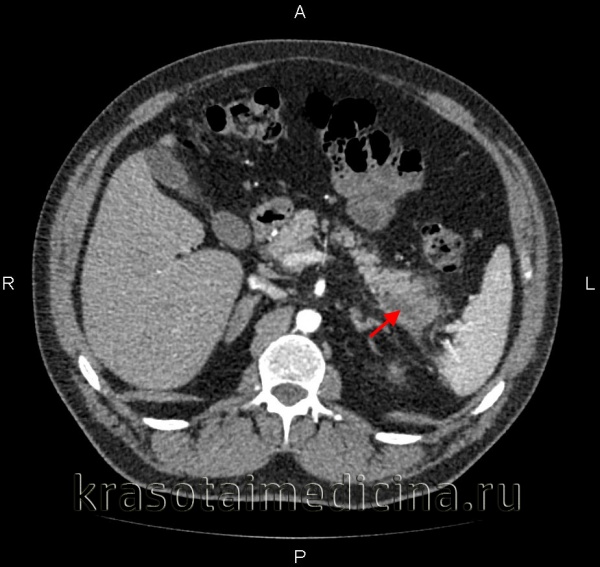

КТ органов брюшной полости. Панкреатит (в области хвоста поджелудочной железы) с наличием отека ее паренхимы, жидкостного содержимого вблизи ее края, на фоне утолщение фасции Героты слева